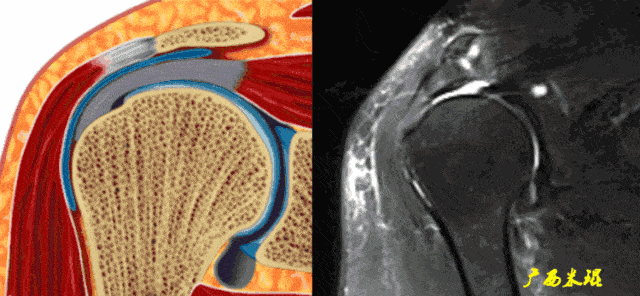

肩袖解剖mr

肩关节mri解剖肩袖损伤诊断技巧